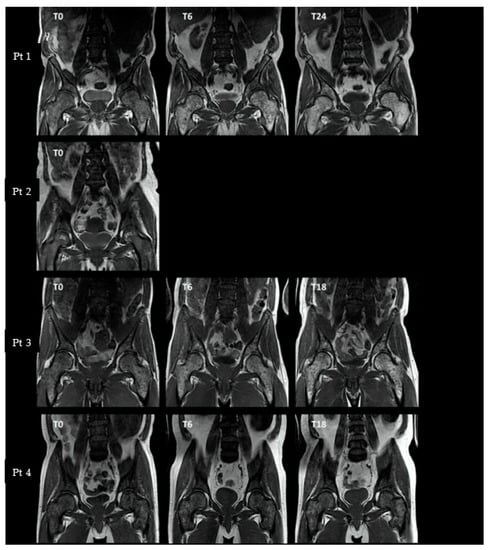

3.3.1. Axial and Proximal Femoral T1-Weighted MRI

| Pt 1 | Pt 2 | Pt 3 | Pt 4 | |

|---|---|---|---|---|

| Sex | male | female | male | male |

| Age at T0, years | 75 | 64 | 47 | 65 |

| Time since diagnosis, months | 31 | 2 | 30 | 262 |

| Driving mutation | JAK2V617F | JAK2V617F | JAK2V617F | calreticulin |

| Prior treatment | - | - | - | - |

| Comorbidities | - | atrial fibrillation, hypertension | - | - |

| Transfusion history | no | yes (2 months) | no | no |

| DIPSS plus risk score at T0 | int-1 | int-2 | int-1 | int-2 |

| Main reason for treatment | abd. discomfort | night sweats, itching | night sweats, abd. discomfort | night sweats, weight loss |

| Ruxolitinib starting dose, mg/day | 40 | 40 | 40 | 40 |

| Dose adjustments (reason) | no | Dose decrease to 5 mg/day (cytopenia) | no | Dose decrease to 20 mg/day (anemia) |

| Grade ≥ 3 adverse events | no | neutropenia | no | anemia |

| Blood transfusions since T0 | no | yes | no | yes |

| Follow-up | deceased | transformation AML | alive | alive |